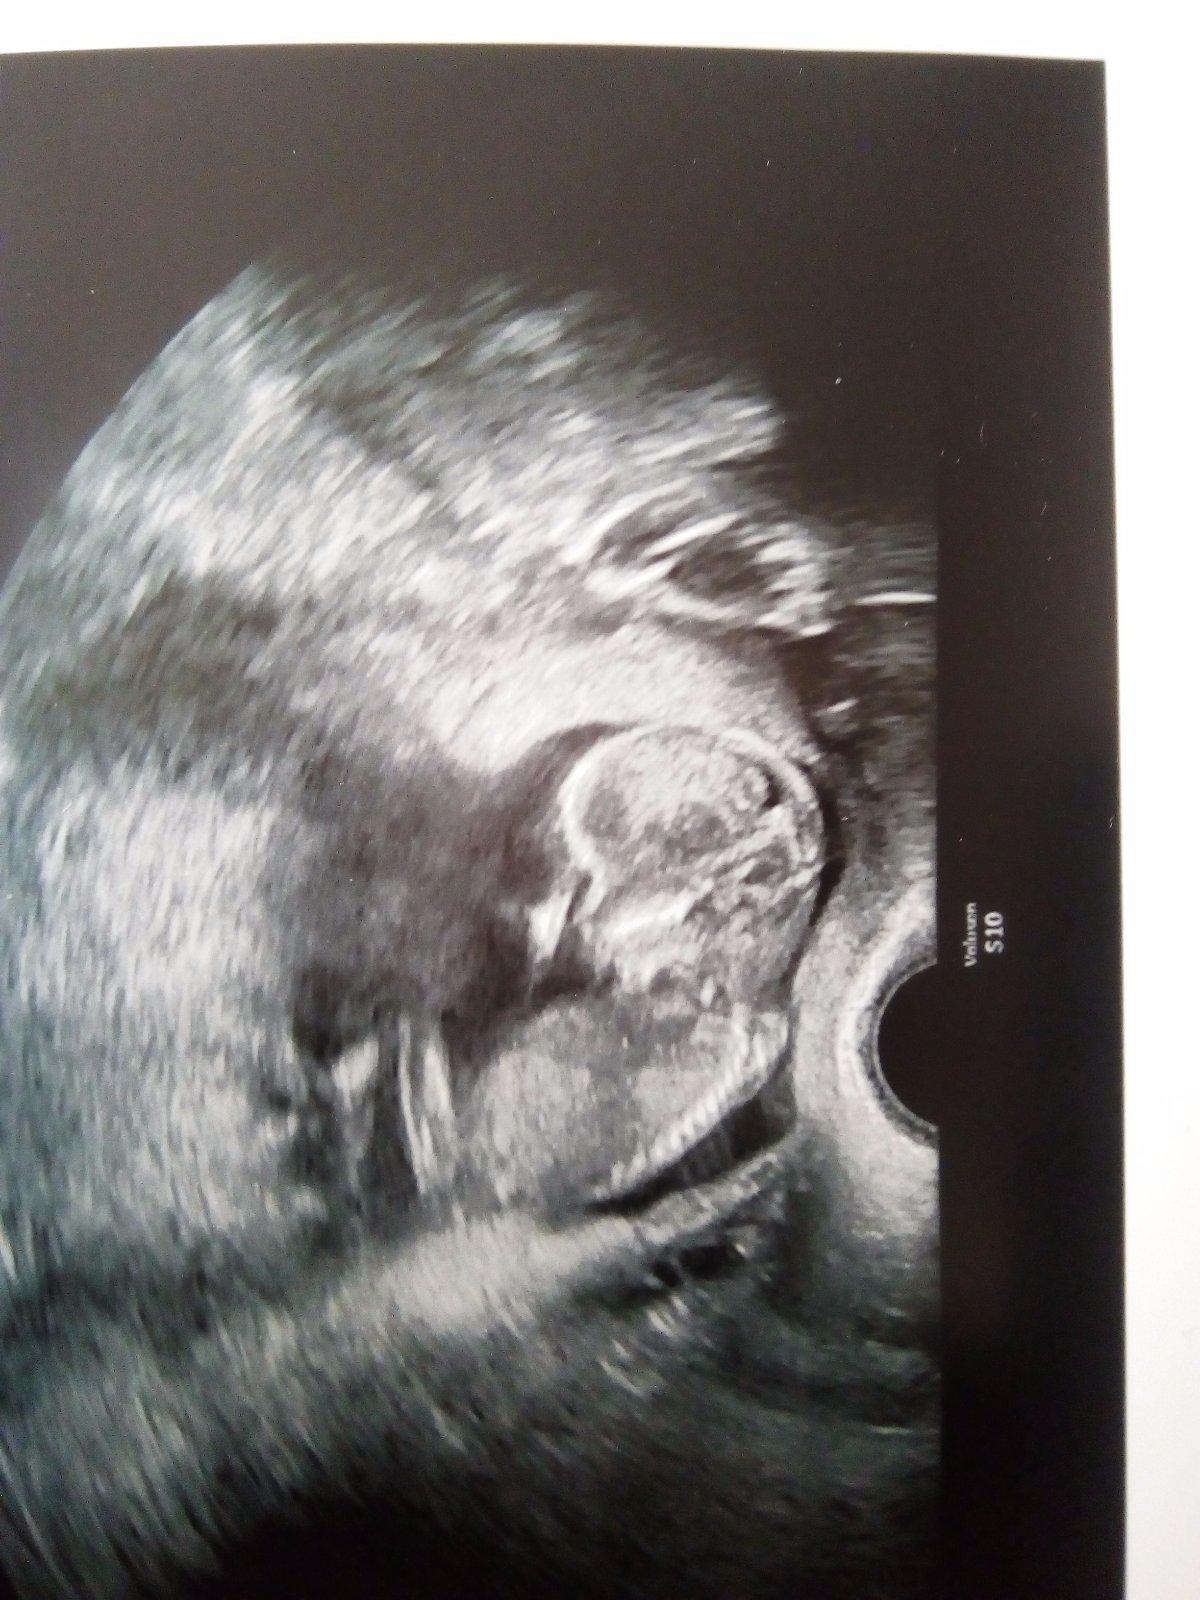

@jullli tak to je super, ze jste dopadli tak krasne. Takze se mimo neukazalo jo?